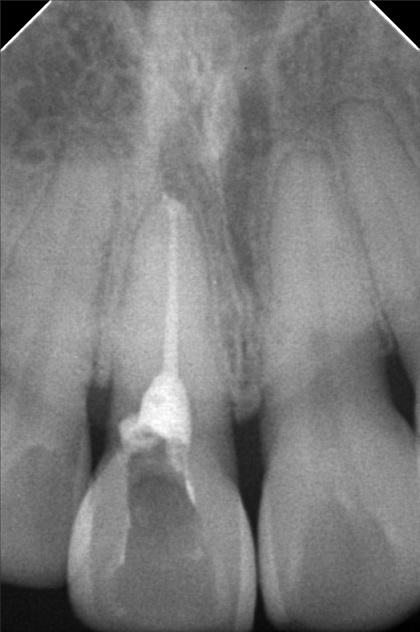

- Procedure

- 5/21/22- OP & XRAY 6/14/22 - RCT / Eugenol 6/21/22- EDTa / tf 8/17/22 - FILE #25 20mm; Irrigate/ EDTA/ TF 8/20/22- guttapercha 30/ 21.5mm/ obturation with MTA veneer 11 shade- opaquer/ A3 cervical body A2/ insical 08/08/23-LC #35 Distal,Cervical Caoh/LC #37 Mesial,OP,X-ray/anesthesia 08/26/23- for RCT #35 / Check up 06/14/24 Op(heavy) #35 alumina crown 06/21/24 Install of crown 12/20/24 OP heavy LC #34 occ. deep 05/15/26 OP w/airpolish